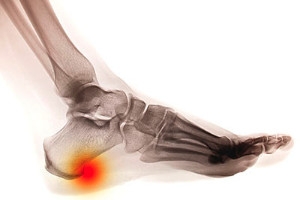

What Causes Heel Spurs?

The condition that is known as a heel spur can cause pain and discomfort. It happens as a result of a calcium deposit that forms between the arch and the heel of the foot. The symptoms that are often associated with this condition can include difficulty in walking barefoot, pain in the heel and surrounding areas, and swelling and inflammation. It can develop with muscle and ligament tension, which may cause the soft tissues to wear out. People who frequently participate in sporting activities that involve running and jumping may be prone to developing heel spurs. It is beneficial to wear shoes that have adequate cushioning in the heel area, in addition to resting and elevating the foot as often as possible. If you have developed a heel spur, it is advised that you speak to a podiatrist who can recommend treatment options that are correct for you.

Heel spurs can be incredibly painful and sometimes may make you unable to participate in physical activities. To get medical care for your heel spurs, contact Dr. Michael T. Hames from Florence Foot Center. Our doctor will do everything possible to treat your condition.

Heels Spurs

Heel spurs are formed by calcium deposits on the back of the foot where the heel is. This can also be caused by small fragments of bone breaking off one section of the foot, attaching onto the back of the foot. Heel spurs can also be bone growth on the back of the foot and may grow in the direction of the arch of the foot.

Older individuals usually suffer from heel spurs and pain sometimes intensifies with age. One of the main condition's spurs are related to is plantar fasciitis.

Pain

The pain associated with spurs is often because of weight placed on the feet. When someone is walking, their entire weight is concentrated on the feet. Bone spurs then have the tendency to affect other bones and tissues around the foot. As the pain continues, the feet will become tender and sensitive over time.

Treatments

There are many ways to treat heel spurs. If one is suffering from heel spurs in conjunction with pain, there are several methods for healing. Medication, surgery, and herbal care are some options.

If you have any questions feel free to contact our office located in Florence, Alabama . We offer the latest in diagnostic and treatment technology to meet your needs.